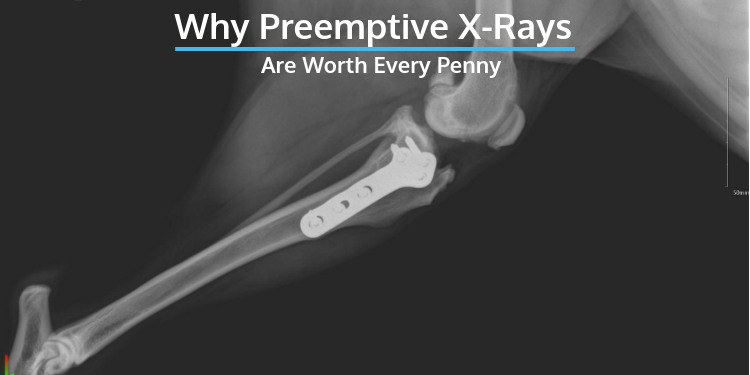

Prophylactic X Rays Are Worth Every Penny Topdog Health

Broken front paw cat X-ray. These radiographs x-rays were acquired using a oblique dorsal-palmar angle. During x-rays the cat must be still and the people performing the procedure will position her so that the x-ray beam will travel through the.

By Totori December 5 2021 136 am updated December 5 2021 1024 am 169 Views 3 Votes. Cat x-rays usually proceed as follows. On the left you can see the Xray of a declawed cat while the cat on the right is completely intact and doing well.

The X Ray On The Left Is Of A Declawed Cat S Paw The One On The Right Is Of A Cat With Intact Claws A Declaw Is An Amputation And Not Always A